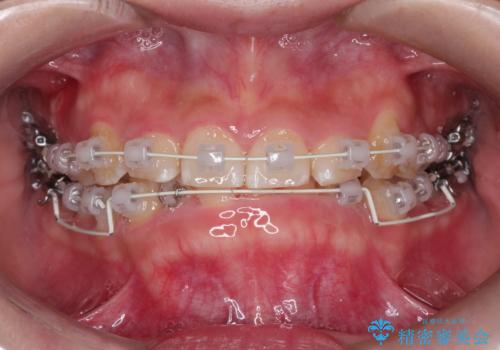

【審美ワイヤー】前歯が見えない。深い噛み合わせの治療

- 前歯の凸凹と深い噛み合わせを主訴に来院されました。

下の前歯が見えないほどのディープバイト症例でした。

ワイヤー矯正にて下顎前歯の圧下と臼歯部の挺出を効率的に行うことができました。

下顎前歯も綺麗に見えるようになり大変満足していただきました。